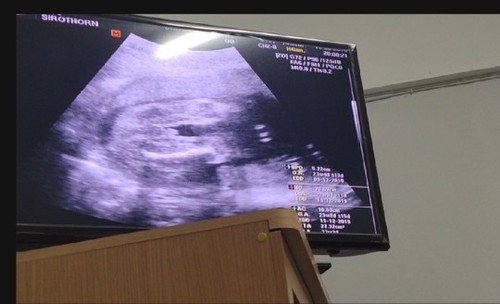

ชี้โด่ เห็นไข่ชัดเจนเลย บ้านนี้อยากได้ลูกชาย แต่ได้ลูกสาวจ้า เพศไหนก็รักลูกเหมือนเดิม 😍❤😘

แบบนี้ก็ลูกชายชัวร์ใช่ไหมค่ะแม่ดูไม่ค่อยเป็นเลย

ได้ลูกชายเหมือนกันค่ะ ตอนซาวน์ หมอบอก นั่นไงโด่ๆ 555

เราก็เห็นจากมุมนี้เช่นกัน 5555 แท่งมหัศจรรย์